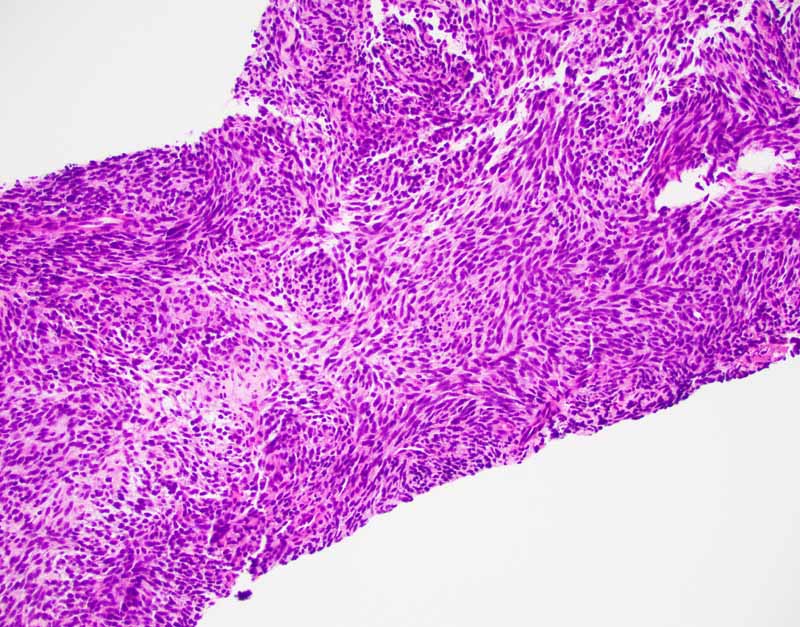

Histology of the Case: The lesion is an encapsulated neoplasm a glandular component and a myxoid component (Panel I and J). The two comonents are well demarcated without transition from one into another. Although the myxoid component (Panel K and L) is not present in the cell block of the FNA, the myxoid substance of the FNA comes from this myxoid component. The glandular component (Panel M, N, O, P) is composed of well formed glands with PAS positive mucoid content in the lumen (Panel Q). In between the well formed glands are spindle cells with nuclear features identical to that of the glands (S in Panel N). This component is present in the cell block of the FNA and is the major clue for the diagnosis.

The classic biphasic type is readily recognizable by the presence of epithelial component in a background of spindle cells similar to fibroblasts. Well-defined sharp transition rather than gradual transition is typical between the epithelial and spindle cell component. The glandular growth pattern can vary from obvious to vague and, in the later case, clefts resulted from shrinkage due to processing must not be mistaken as genuine glandular lumens. The glandular epithelial cells are usually cuboidal to columnar. Secretions within the lumen can be seen and squamous metaplasia may be present. The spindle cell component is typically composed of monotonous well-oriented plump spindle cells with indistinct cytoplasm and oval to elongated hyperchromatic nuclei. Fibrotic areas with hyalinization and myxoid changes can be found. In about 20% of cases, calcifications with or without ossification is present and act as a good diagnostic clue. Substantial number of mast cell is another diagnostic clue.